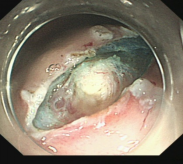

肝硬化食管和胃底静脉曲张破裂出血的内镜下组织胶注射和套扎序惯治疗